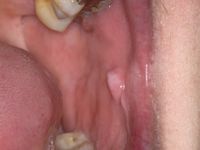

![Morsicatio buccarum (click on photo to enlarge) [source: www.huidziekten.nl] Morsicatio buccarum](../../../images/morsicatio-buccarum-1z.jpg) |

| morsicatio

buccarum |